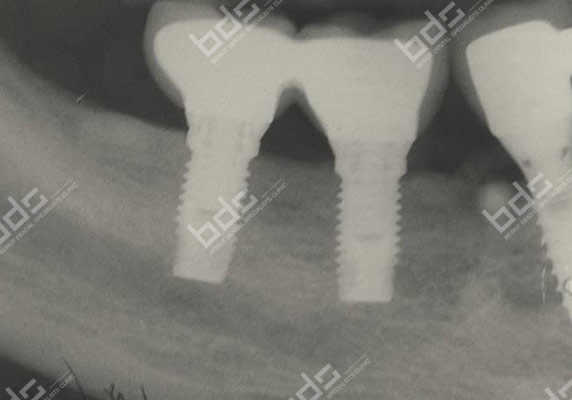

Dental Implants

Dental implants is a highly predictable procedure for the replacement of missing teeth, restoring in a very effective way both function and aesthetics. Dentures ,when loose, can cause severe personal and social handicaps that can be overcome by using implant supported fixed restorations. Implants can also serve to replace one or several teeth and save healthy adjacent teeth from being used as support for fixed bridges. The procedure can be very simple or more complex depending on the severity of the case. Implants used nowadays are mostly made of medical grade titanium. They are placed in the jaw and connected to abutments to serve as support for crowns or bridges.

Implant supported crowns are so natural looking ! Cad Cam technologies and innovative restorative materials give to the crown a perfect esthetic result. You will forget that you ever lost a tooth. your confidence is regained and your self image is completely restored. you do not need to hide your smile anymore nor feel embarrassed because of ill-fitting dentures. you may have had difficulty chewing. You will regain your full function! Implant-supported crowns will look and feel just like your own!

Your treatment needs to be properly planed and the implants and crowns placed under the best conditions to ensure long term success. With diligent maintenance, implants can last a lifetime. Long-term studies show very high success rates.

Because a dental implant will replace your tooth root, the bone is preserved. With a bridge, some of the bone that previously surrounded the tooth resorbs in time , part of a natural remodeling process Dental implants integrate with your jawbone, helping to keep the bone healthy and intact.

A single implant can be more esthetic and easier to keep clean than a bridge. Also, after several years of function, gums can recede around a bridge causing unesthetic exposure of the bridge margins. Resorbed bone beneath the bridge can be the cause of an unattractive smile. Also, the cement holding the bridge in place can wash out, allowing bacteria to proliferate unreached by the tooth brush resulting in decay of the anchoring teeth and bridge loss